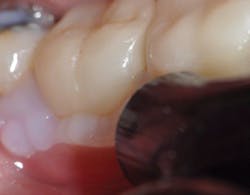

Figures 5 and 6: Tack-cure Variolink Esthetic cement for two seconds per quarter for ease of cement cleanup. After cleanup, place liquid strip (glycerin gel) to protect the oxygen inhibitor layer. Then final cure all of the crown for 10 seconds, followed by final cleanup; adjust and polish.

Adhesive resin cement is a must to have available for all ceramic restorations, veneers, inlays, and onlays. Having this in light-cure and dual-cure materials provides flexibility of technique (figures 5 and 6). Having an RMGI cement offers a simplified technique along with fluoride protection, and having a conventional cement where enhanced retention and bond strength are not needed provides a second choice.3,8 For metal crowns, dual-cure and self-curing cements are also options. However, one may want to avoid the challenge of future crown removal such as when adhesive resin cement is combined with cutting off ceramic crowns, thus considering conventional cements where retention is not an issue and color modification is not needed.